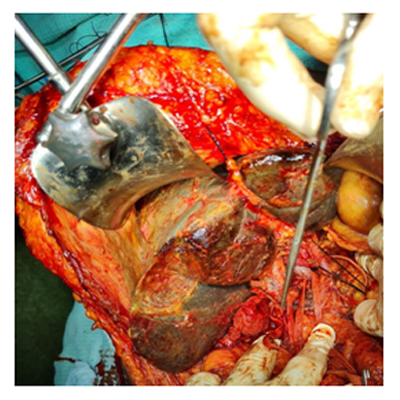

We have state of the art operating theatre with advanced surgical equipments. We have a Karl Storz Spies advanced HD laparoscopy operating system in addition to a 3 chip laparoscopy. We have installed advanced vessel sealing devices like Gen 11 harmonic scalpel, Ligasure from Valley Lab & Argon plasma coagulator. There is a recent addition of Cavitron Ultrasonic Aspirator (CUSA) system into our surgical armamentarium. We have the most recent powered Echelon endo-stapling devices. In addition to all these we have a constant supply of various types of advanced stapling devices for GI surgeries. Our endoscopy machines are having high definition with FICE Technology. Last but not the least we have semi flexible Ureteroscopy for managing common bile duct stones.

CAVITRON ULTRASONIC ASPIRATOR USED FOR LIVER RESECTION

LIVER RESECTION DONE USING CUSA

ARGON PLASMA COAGULATOR